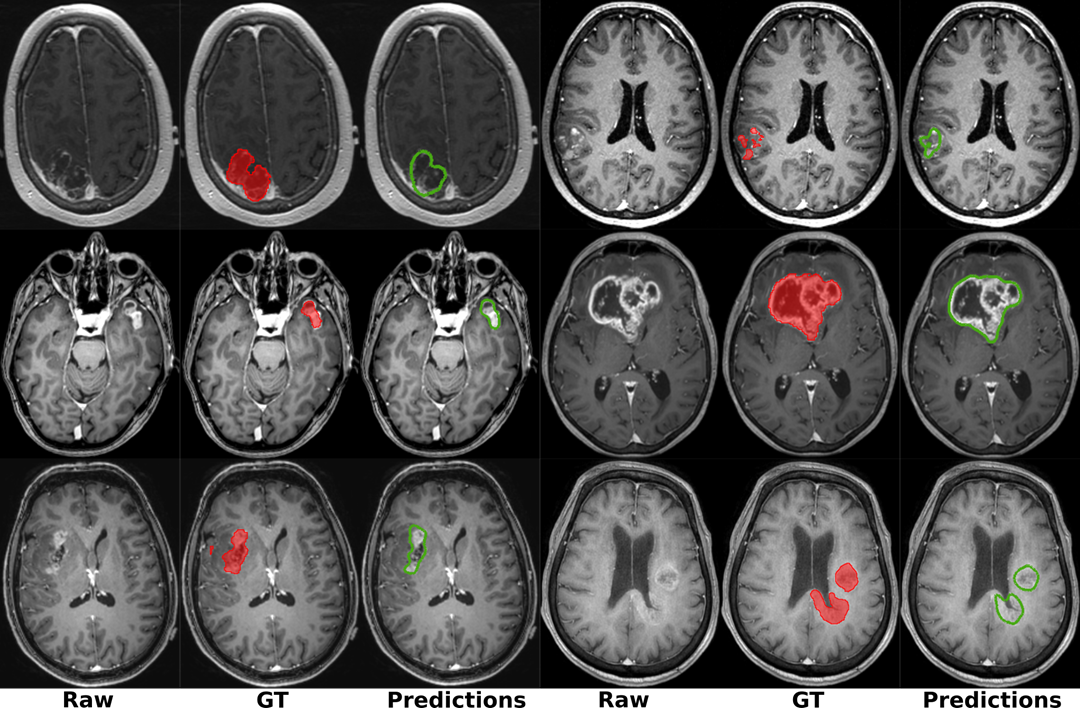

Hovedmålet er å få ny kunnskap om sammenhengen mellom kliniske og radiologiske funn, sykdomsforløp og behandlingsrespons hos hjernesvulstpasienter. Dette vil kunne føre til mer persontilpasset behandling. Vi bruker maskinlæring til å trene modeller for automatisk bildeanalyse og prediksjon av overlevelse og behandlingsrespons basert på data fra den enkelte pasient i kombinasjon med data fra hundrevis av tidligere pasienter.

Omtrent 1000 personer får kreft i sentralnervesystemet i Norge hvert år. Hjernekreft er den krefttypen med høyest dødelighet hos personer under 40 år og en av de vanligste krefttypene hos barn. Svulstene er svært forskjellige og det er stor variasjon i aggressivitet, vekstmønster og behandlingsrespons. Symptomer og prognose varierer mye og kan være vanskelig å forutsi selv for erfarne leger. For å få bedre kunnskap om sammenhengen mellom egenskaper ved svulsten, symptomer, sykdomsforløp og behandlingsrespons ble Midtnorsk hjernesvulstregister og biobank etablert i 2015 av klinikere og forskere ved St. Olavs hospital og NTNU. Basert på data fra dette registeret, sammen med data fra nasjonale og internasjonale samarbeidspartnere, utvikler forskere ved SINTEF modeller for automatisk bildeanalyse samt prediksjon av prognostiske faktorer og sykdomsforløp basert på kunstig intelligens og maskinlæring.

(1) Utvikle verktøy for kvantitativ radiologisk vurdering av hjernesvulster. Dette inkluderer segmentering av pre-operative, intra-operative og post-operative MR/US/CT bilder for å